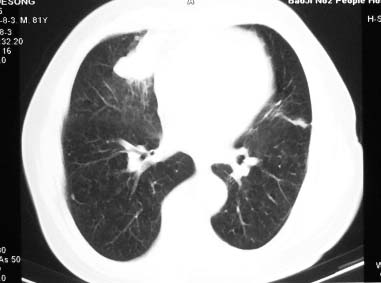

81 男 以头昏入院

两肺多发异常密度,其中双上肺病变主要为纤维增殖性改变;右中肺内侧段病变密度相对均匀,无恶性特征,周围可见卫星灶和浸润表现,邻近胸膜稍增厚,所见纵隔层面无肿大淋巴结和胸腔积液。提示结核性改变。如果可能建议强化。

右肺中叶团片影,似多病灶融合而成,密度不均匀,边界清楚,周围见明显的索条及小结节,左肺亦见斑片影,纵隔窗未见肿大淋巴结.多考虑:肺内慢性炎性病变伴纤维化.

两肺多发异常密度,其中双上肺病变主要为纤维增殖性改变;右中肺内侧段病变密度相对均匀,无恶性特征,周围可见卫星灶和浸润表现,邻近胸膜稍增厚,所见纵隔层面无肿大淋巴结和胸腔积液。提示结核性改变.

符合多叶多段多形态的特点.

右肺中叶软组织块(挑剔一下纵隔窗窗宽不理想),其周围可见多个类圆形结节,右肺上叶尖段见斑片、索条状致影,左肺小结节。

1.右肺周围型肺癌伴肺内转移;

2.右肺上叶陈旧性结核;

3.左肺炎性结节;

右肺中叶软组织块,其周围可见多个类圆形结节,右肺上叶尖段见斑片、索条状致影,左肺小结节,见分叶、毛刺及胸膜凹陷征。1.左肺周围型肺癌伴右肺内转移; 2.右肺上叶陈旧性结核。